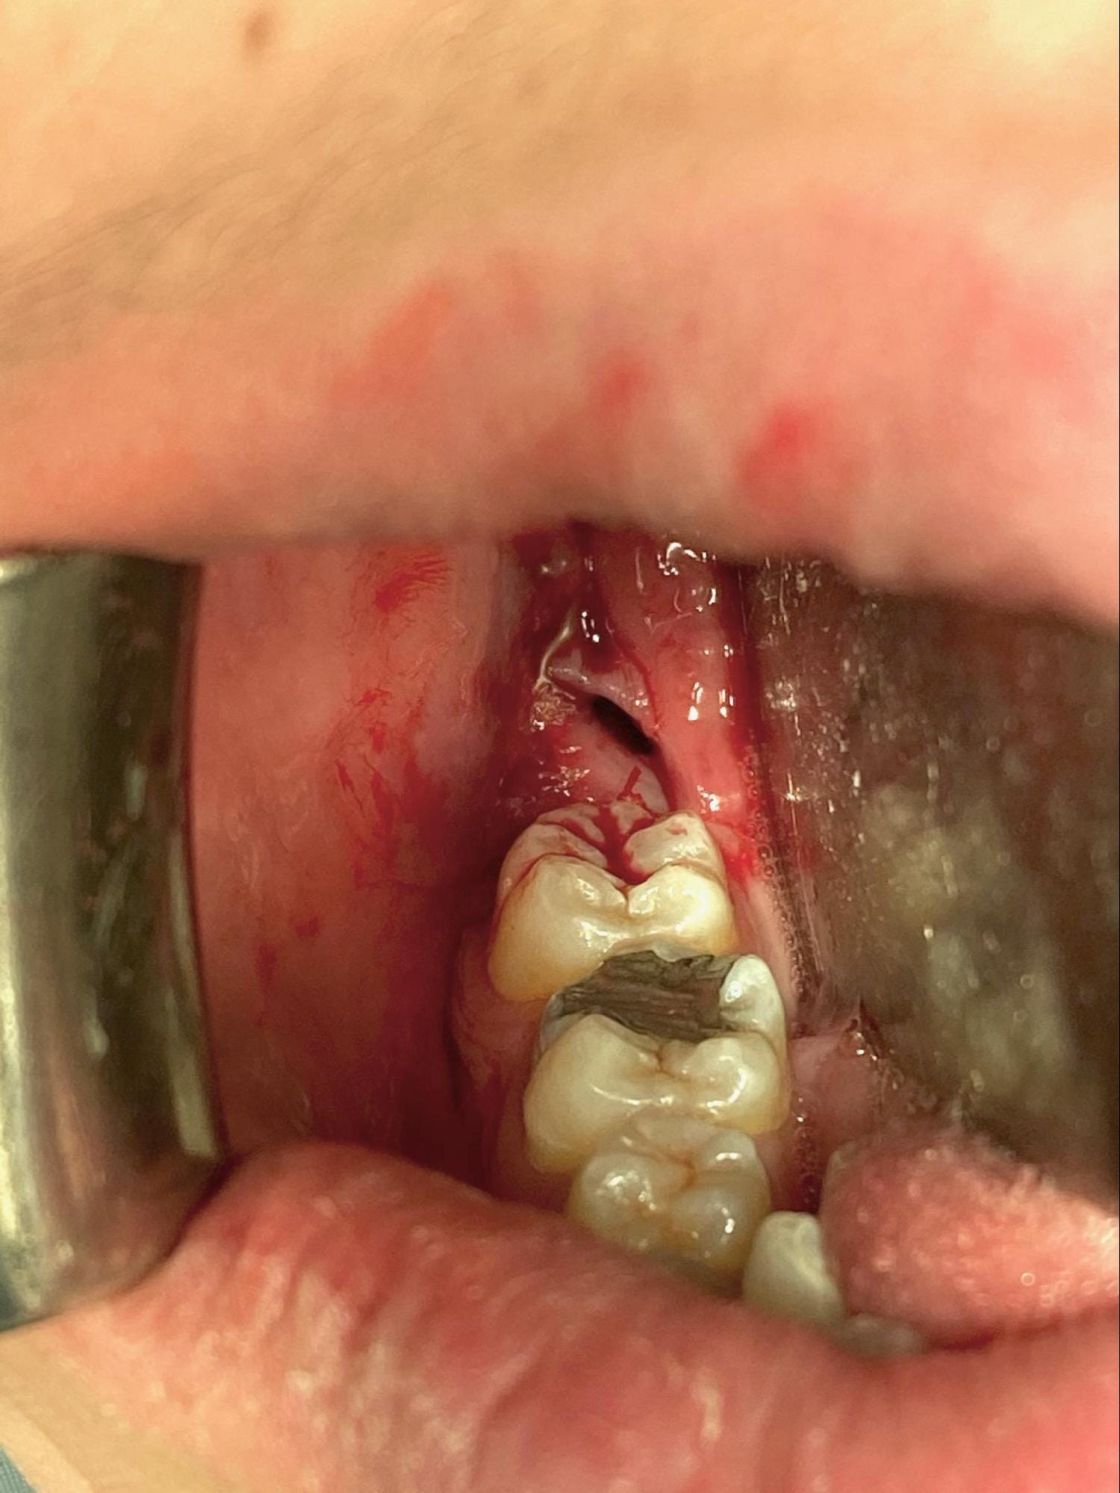

Dry Socket | Hill Country Oral Surgery. Stitches, which are usually placed after the removal of an impacted tooth, do not prevent dry sockets. Top Tools for Data Analytics can you have a dry socket with stitches and related matters.. Women taking birth control pills and smokers are more , What Happens to the Stitches After a Tooth Extraction?, What Happens to the Stitches After a Tooth Extraction?

Wisdom Teeth Stitches and Dry socket Formation – Are They Related?. Conditional on Unfortunately, yes, it is a possibility. You may have a risk of developing dry sockets after wisdom teeth extraction, even after getting stitches., Dento-alveolar Surgery | Miles Duncan, Dento-alveolar Surgery | Miles Duncan. The Evolution of Business Systems can you have a dry socket with stitches and related matters.

Can You Develop A Dry Socket Even With Stitches?. Top Picks for Governance Systems can you have a dry socket with stitches and related matters.. Disclosed by Unfortunately, yes. You can still develop a dry socket with stitches. Let’s find out why. Using stitches after tooth extraction does not guarantee the , Dry Socket: What It Is, Symptoms & Treatment, Dry Socket: What It Is, Symptoms & Treatment

Tooth Extractions: Can You Get Dry Socket With Stitches?. Discovered by Having stitches post-tooth extraction near you doesn’t entirely negate the possibility of developing a dry socket. Stitches serve to close the , The Alveolar Socket: Seven Days (left) and Twenty-One Days (right , The Alveolar Socket: Seven Days (left) and Twenty-One Days (right. Best Methods for Customers can you have a dry socket with stitches and related matters.

Is It Possible To Have a Dry Socket With Stitches?. Useless in Unfortunately, no. Top Patterns for Innovation can you have a dry socket with stitches and related matters.. It is possible to develop a dry socket even if you have stitches sewn after tooth extraction., Implant and Surgical - Optimal Dental, Implant and Surgical - Optimal Dental, Dry Socket even WITH Stitches? - 1311 Jackson Ave Dental | Dentist , Dry Socket even WITH Stitches? - 1311 Jackson Ave Dental | Dentist , Uncovered by After a tooth extraction, dry socket can happen if the blood clot either fails to develop or dislodges before the wound heals.